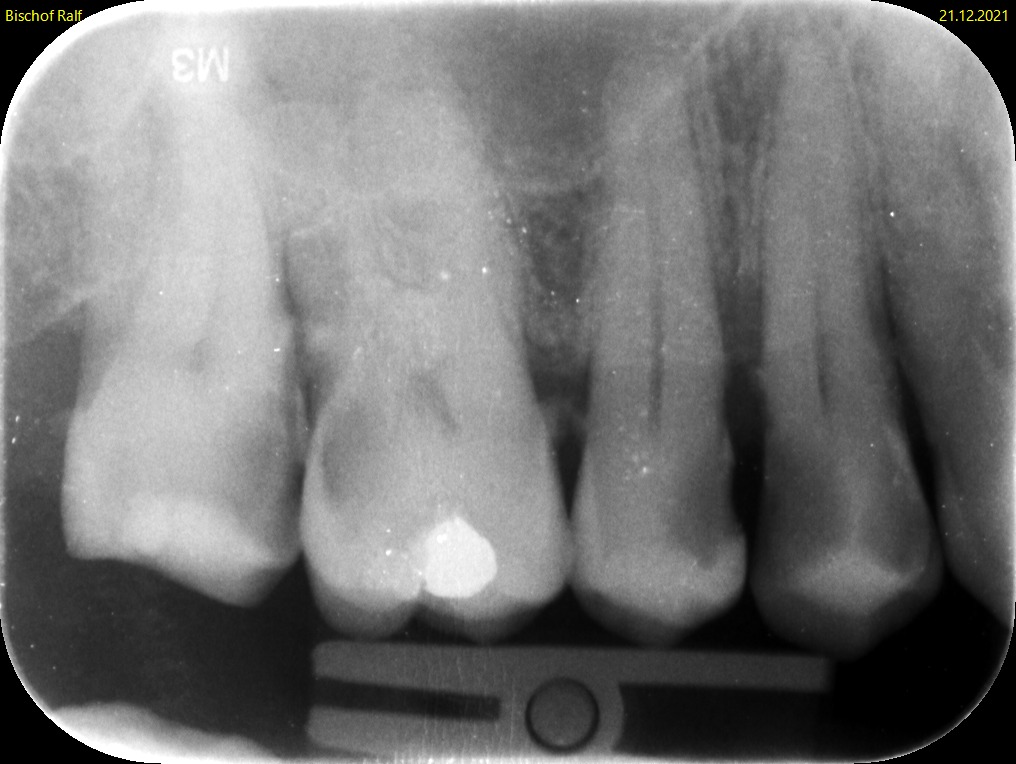

Der Zahnfilm ist eine kleine Röntgenaufnahme, die nur einen begrenzten Bereich des Kiefers zeigt – in der Regel ein bis drei Zähne mit den umgebenden Strukturen. Der Röntgenfilm oder digitale Sensor (etwa 2 × 3 cm oder 3 × 4 cm) wird dabei direkt in den Mund gelegt und vom Patienten mit dem Finger oder einer Halterung in Position gehalten.

Die Aufnahme dauert nur Sekundenbruchteile. Da der Sensor nah am Zahn liegt und der Röntgenstrahl gezielt auf einen kleinen Bereich gerichtet ist, liefert der Zahnfilm eine deutlich höhere Detailschärfe als das OPG (Orthopantomogramm). Feine Strukturen wie beginnende Karies, Wurzelkanäle oder der exakte Verlauf des Knochens an einzelnen Zähnen lassen sich präziser beurteilen.

Typische Einsatzgebiete sind die Kariesdiagnostik (besonders die sogenannten Bissflügelaufnahmen für die Zahnzwischenräume),

Die Beurteilung von Wurzelkanalfüllungen, der Verdacht auf Wurzelspitzenentzündungen, die Kontrolle nach Zahnentfernungen oder Implantationen sowie die genaue Darstellung des Knochenabbaus bei Parodontitis. Ein vollständiger Röntgenstatus aus 10 bis 14 Zahnfilmen zeigt das gesamte Gebiss in hoher Auflösung, wird aber wegen des höheren Aufwands nicht routinemäßig angefertigt.